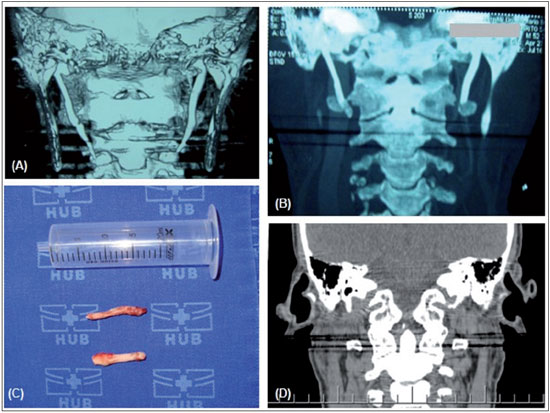

Radiography and computed tomography of the neck showed elongation and ossification of the styloid processes of the temporal bone. The right styloid process measured 5.7 cm and the left measured 4.9 cm, which was compatible with Eagle's syndrome (Figures 1A and 1B).

Surgery was performed for bilateral resection of the stylohyoid ligament by using a transoral endoscopic access route. However, the patient continued to present preauricular pain with a burning sensation irradiating to the sides of the neck and temporal region, predominantly on his left side. Another computed tomography scan was produced, which showed elongation and ossification of the styloid processes of the temporal bone, with the right side measuring 4.4 cm and the left side measuring 3.9 cm. This suggested that the base of the styloid process continued to be present bilaterally. The patient then underwent lateral cervicotomy with resection of the stylohyoid process, which partially resolved his painful condition (Figures 1C and 1D).

FIGURE 1. (A) Computed tomography (CT) scan of the neck showing elongation and ossification of the styloid processes of the temporal bone. The right styloid process measures 5.7 cm and the left measures 4.9 cm, which is compatible with Eagle's syndrome. (B) CT scan of the neck after intraoral styloidectomy, showing ossification of the styloid processes. The right styloid process measures 4.4 cm and the left measures 3.9 cm, thus suggesting that the base of the styloid process is present on both sides. (C) Surgical specimen after extraoral styloidectomy: right and left styloid processes. (D) CT scan of the neck after extraoral styloidectomy, showing the absence of elongation of the styloid processes on both sides.